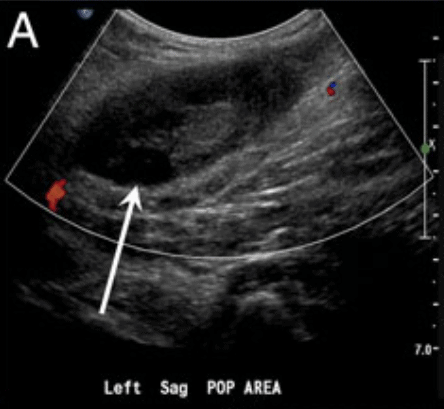

9 Move the probe into the posterior crease of the knee and scan 2 cm above and below to find the popliteal vein. Remember "Pop on Top." Apply compression.

16 A Baker’s cyst is a fluid-filled cyst in the popliteal bursa and can be a false positive.

It appears as a circular anechoic mass with sharply defined borders in both the longitudinal and transverse view. On Color Doppler, there should be no flow.